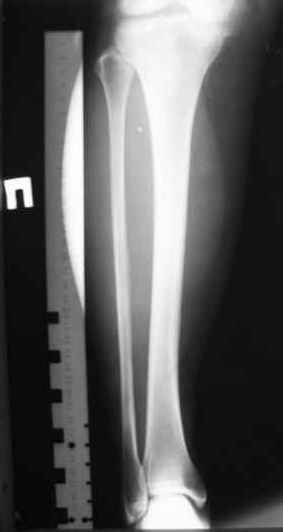

Здравствуйте уважаемые коллеги. Позвольте поделиться опытом применения интрамедуллярного остеосинтеза большеберцовой кости имплантатами компании ?Остеомед" с запатентованной прицельно-навигационной системой для дистального блокирования ?Интерлок". Для определения длинны и диаметра стержня использовали линейку-шаблон, позволяющей с легкостью рассчитать длину и диаметр стержня с проекцинно искаженными размерами, как конечности, так и линейки-шаблона.Дистракцию производили с помощью спицевого дистрактора с последующей закрытой репозицией отломков винтами Шанца. Все основные этапы производили по методике АО, гарантированное дистальное блокирование достигается за счет центрирования отверстий, путем контролирования смещения стержня в костномозговом канале в сагиттальной плоскости. Клинический пример:Больная Я. 45 лет, пострадала в результате случайного падения на улице 19.12.2005., имеет место открытый 1 степени перелом обеих костей левой голени со смещением отломков.произведена закрытая репозиция перелома с последующим введением стержня (на данном этапе производился рентген-контроль)Убедившись в достаточной репозиции перелома, произведено дистальное и проксимальное блокирование интрамедуллярного стержня.Общее время затраченное на оперативное вмешательство составило 45 минут.